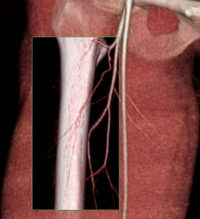

3D-CT-angiogram-planning-for-phalloplasty-skin-flap1 (1).jpg

3D image of a CT angiogram for surgical planning for a phalloplasty skin flap.

OHSU faculty and trainees are dedicated to providing high quality and inclusive care for trans and gender diverse individuals. For example, imaging plays an important role in planning for gender affirming surgeries (see example image). Screening mammograms are also recommended for transfeminine patients who have been taking hormones for greater than 5 years and for transmasculine patients with history of reduction mammoplasty or no chest surgery. We aim to ensure that all patients feel welcome and cared for.